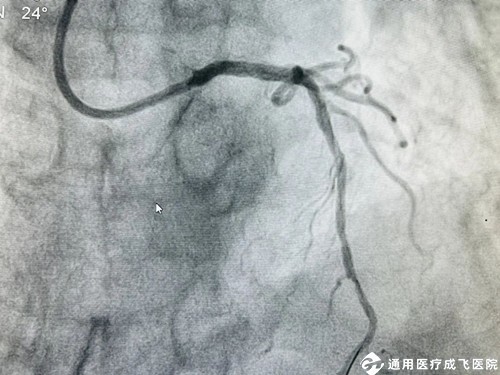

手术中,在王勉教授的指导下,心内科介入团队采用Shockwave 震波技术通过先后触发7个周期(70个脉冲)反复冲击波,以局部高效的震荡形式,对血管内的钙化结构进行“敲打”,在不影响正常血管组织的情况下将钙化结构碎裂,从而打开血管的“紧箍咒”,使血管扩张开,为后续的支架植入和充分扩张提供条件。术中前降支-左主干成功植入长支架1枚,历时仅1小时,病变狭窄明显缓解,管腔面积得到有效恢复,血流通畅。任大爷各项生命体征平稳,一直萦绕心头的“顽石”落了地,择期即将出院。

支架术后